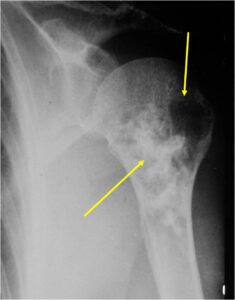

Radiology emulates pathology: Biphasic Tumor

- One region low grade chondrosarcoma

- Second more aggressive area with bone destruction, lysis of calcification, soft tissue mass

- Cortical permeation and a soft tissue mass in 70% of cases

Ill-defined, lytic intraosseous lesion

- Or extraosseous soft tissue mass

- Devoid of calcifications in continuity with lesions having the features of a cartilaginous tumor

Characteristically abrupt transition between chondroid tumor and dedifferentiated, lytic component

Bone may be expanded and adjacent cortex thickened